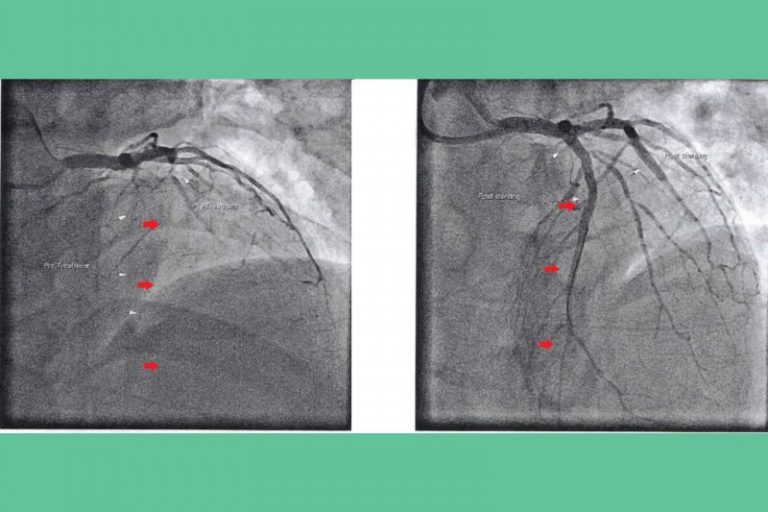

梅醫生指,病人即使完成「通波仔」手術也不是一勞永逸,研究表示有20%至50%術後病人仍有血管再次收窄的風險。因此,術後病人亦需要服用半年或以上的雙重抗血小板藥物、降膽固醇藥等,以減少冠心病再次惡化的機會。